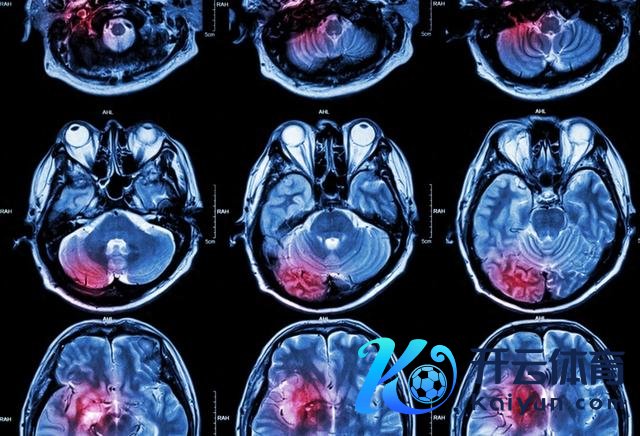

接洽东说念主员在中国12个省市的26家病院开展了一项历时三年的前瞻性、多中心、就地、双盲、安危剂对照素质,招募的成年东说念主(年级≥18岁)在出现症状(或临了一次见好)后48小时内被会诊为有症状的自觉性脑出血(经脑成像证据),导致中度至重度神经毁伤,在好意思国国立卫生接洽院卒中量表中得分至少为8分,或在格拉斯哥晕厥量表中得分在7至14分之间。

在2021年11月24日至2023年12月28日历间,经筛选,在9000名患者中最终得回了1641位参与者(颐养组815例,安危剂组826例)的主要结局数据。接洽团队重心查考患者90天的功能性结局,同期眷注其早期神经功能恶化、糊口率、健康生活质地及180天随访情况。